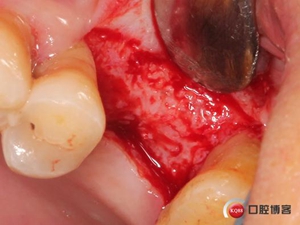

使用水壓系統(tǒng),將1ml左右生理鹽水緩慢注入開孔內(nèi)。

1ml水量便可將頰側(cè)上頜竇膜在還沒有開窗剝離之前就已經(jīng)與上頜竇頰側(cè)骨壁剝離開來,所以此時再在開孔處開窗將不用再擔心會傷及上頜竇膜。用環(huán)切開窗鉆,將種植機調(diào)成反轉(zhuǎn)模式、轉(zhuǎn)速調(diào)至200-500轉(zhuǎn)之間。

無需全部磨穿,剩余一些骨量既可以。

將骨片撬開并取下。

還沒有進行竇膜剝離,頰側(cè)上頜竇膜已經(jīng)和骨壁有效分離。

擴大窗口,進一步剝離竇膜。

植入骨粉。